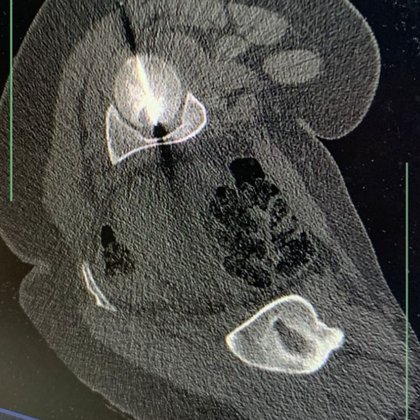

تدخّل علاجيّ نوعيّ في مستشفى الجامعة الأردنيّة باستخدام تقنية الكيّ بالمايكروويف لعلاج ورم في رأس عظم الفخذ https://t.co/Vz930Vu3y9

نفّذ مستشفى الجامعة الأردنيّة مؤخرًا تدخّلًا علاجيًّا متقدّمًا في قسم الأشعة، نجح من خلاله فريقٌ طبيّ متعدّد الاختصاصات في ��لاج ورم عظميّ يقع في موقع شديد الحساسيّة داخل رأس عظم الفخذ لدى مريضة تبلغ...